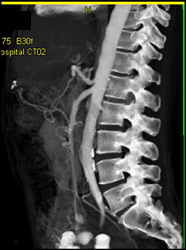

CASE NUMBER 385

Bifid Left Renal Vein